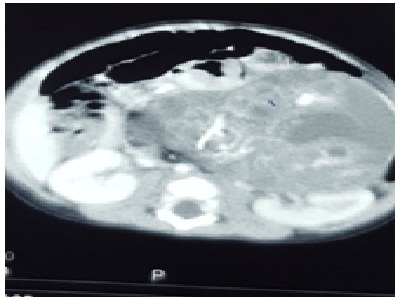

Thăm khám lâm sàng phát hiện bệnh nhân có khối u vị trí dưới hạ sườn phải, không đau, ít di động, kích thước khoảng 13 x 10 cm. Hình ảnh chụp MRI ổ bụng cho thấy một khối u lớn sau phúc mạc, nhiều khả năng là thai nhi, khối u vượt quá đường giữa, đè ép thận trái.

Hình ảnh thai trong thai qua phim chụp MRI. Ảnh: BVCC.